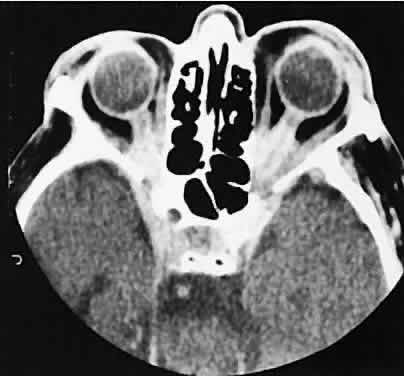

The CT evaluation of orbital myositis may show diffuse irregular enlargement of one or more EOMs; enlargement can be bilateral (Fig. 5). Incontradistinction to Graves' orbitopathy, involvement of the tendinous insertion and edema ofthe adjacent fat may be noted. Other conditions associated with EOM enlargement are listed in Table 2.31–33

Fig. 5. Axial views of orbital myositis. A. Note increased attenuation with enhancement of the thickened medial rectus and thickened scleral insertion. B. Thickening of the medial rectus muscle along the entire length of muscle is more evident.